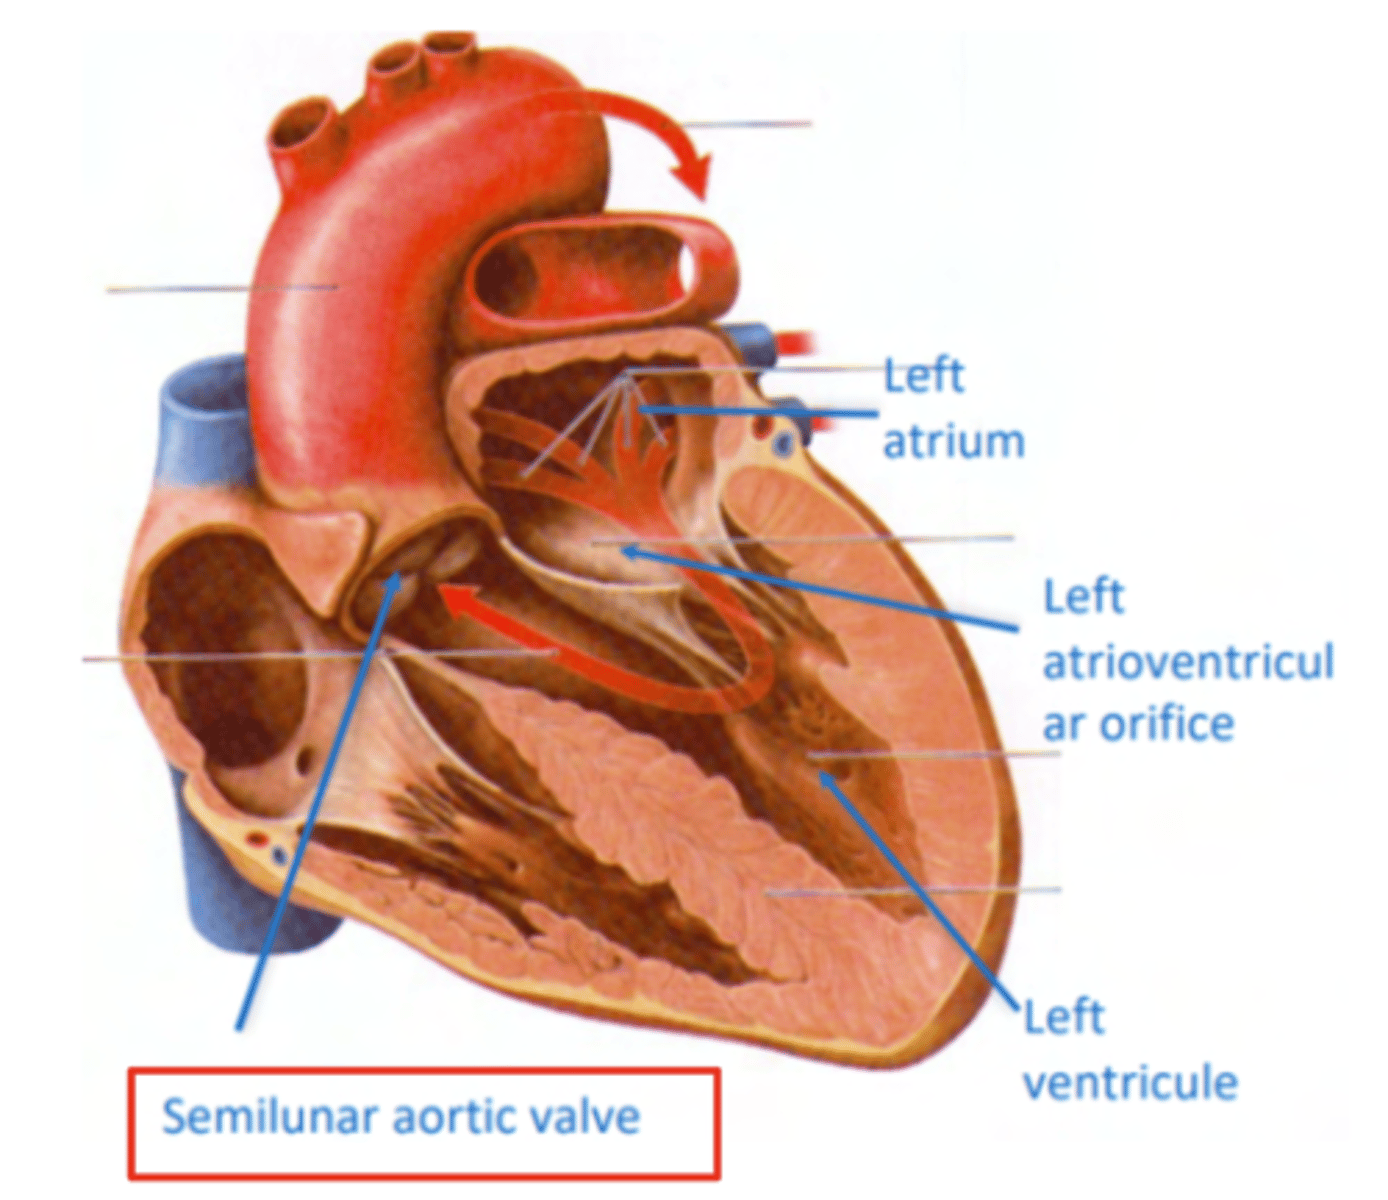

What is the valve in the AV left canal?

. Mitral valve

2 cusps (anterior and posterior) and 2 associated papillary muscles

Why is the left ventricle wall thicker than the right?

It is 3 times thicker than the one on the right, in order to pump blood into the aorta at high pressures

What prevents backflow of blood from the left ventricle to the left atrium?

mitral valve or biscuspid valve

consisting of two cusps connected to two papillary muscles,

What is the valve to prevents reflux in the aorta?

Aortic valve